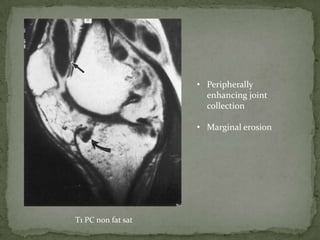

• Peripherally

enhancing joint

collection

• Marginal erosion

T1 PC non fat sat